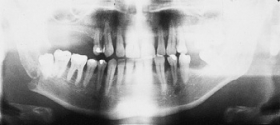

The primary purpose of the consultation is the outpatient follow-up treatment and care of patients who have undergone surgery following bone injuries to the upper and/or lower jaw. In addition to patients with fractures of the facial skull, patients with injuries to the teeth and facial soft tissues are also followed up.

Osteosynthesis procedures are performed at our clinic according to modern international standards. Mini and micro plates made of titanium and special medical steel are used to stabilize the fractured bones. Especially for the treatment of temporomandibular joint fractures a joint plate was developed in our clinic. The development and application of resorbable osteosynthesis materials is at the same time a research task of the clinic.